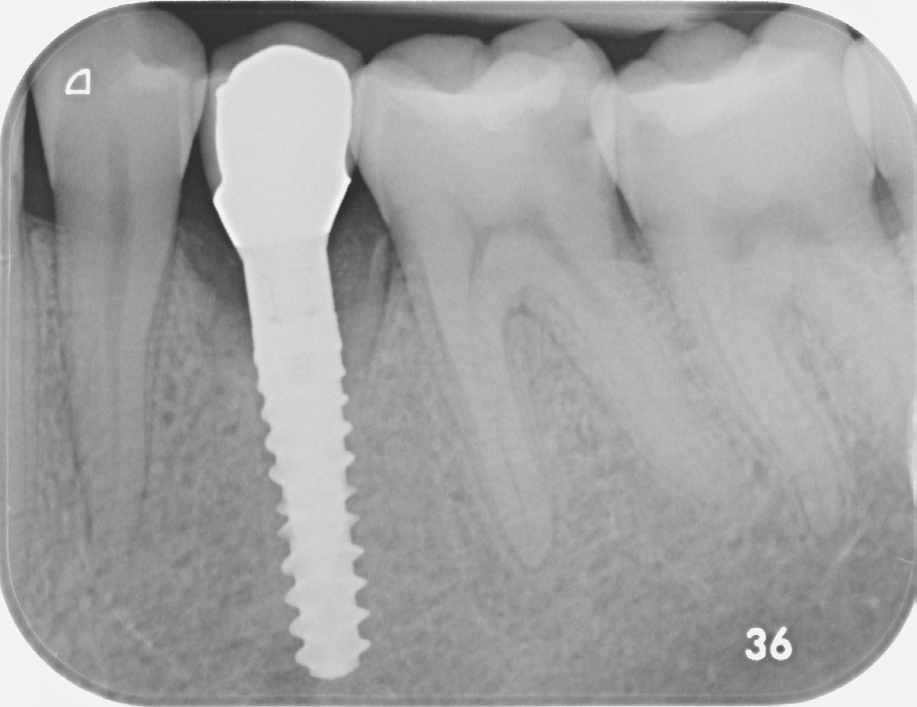

Fig. 6: Postoperative X-ray image of region 34, condition after immediate implantation. |

Figure 10: X-ray image after prosthetic restoration. |